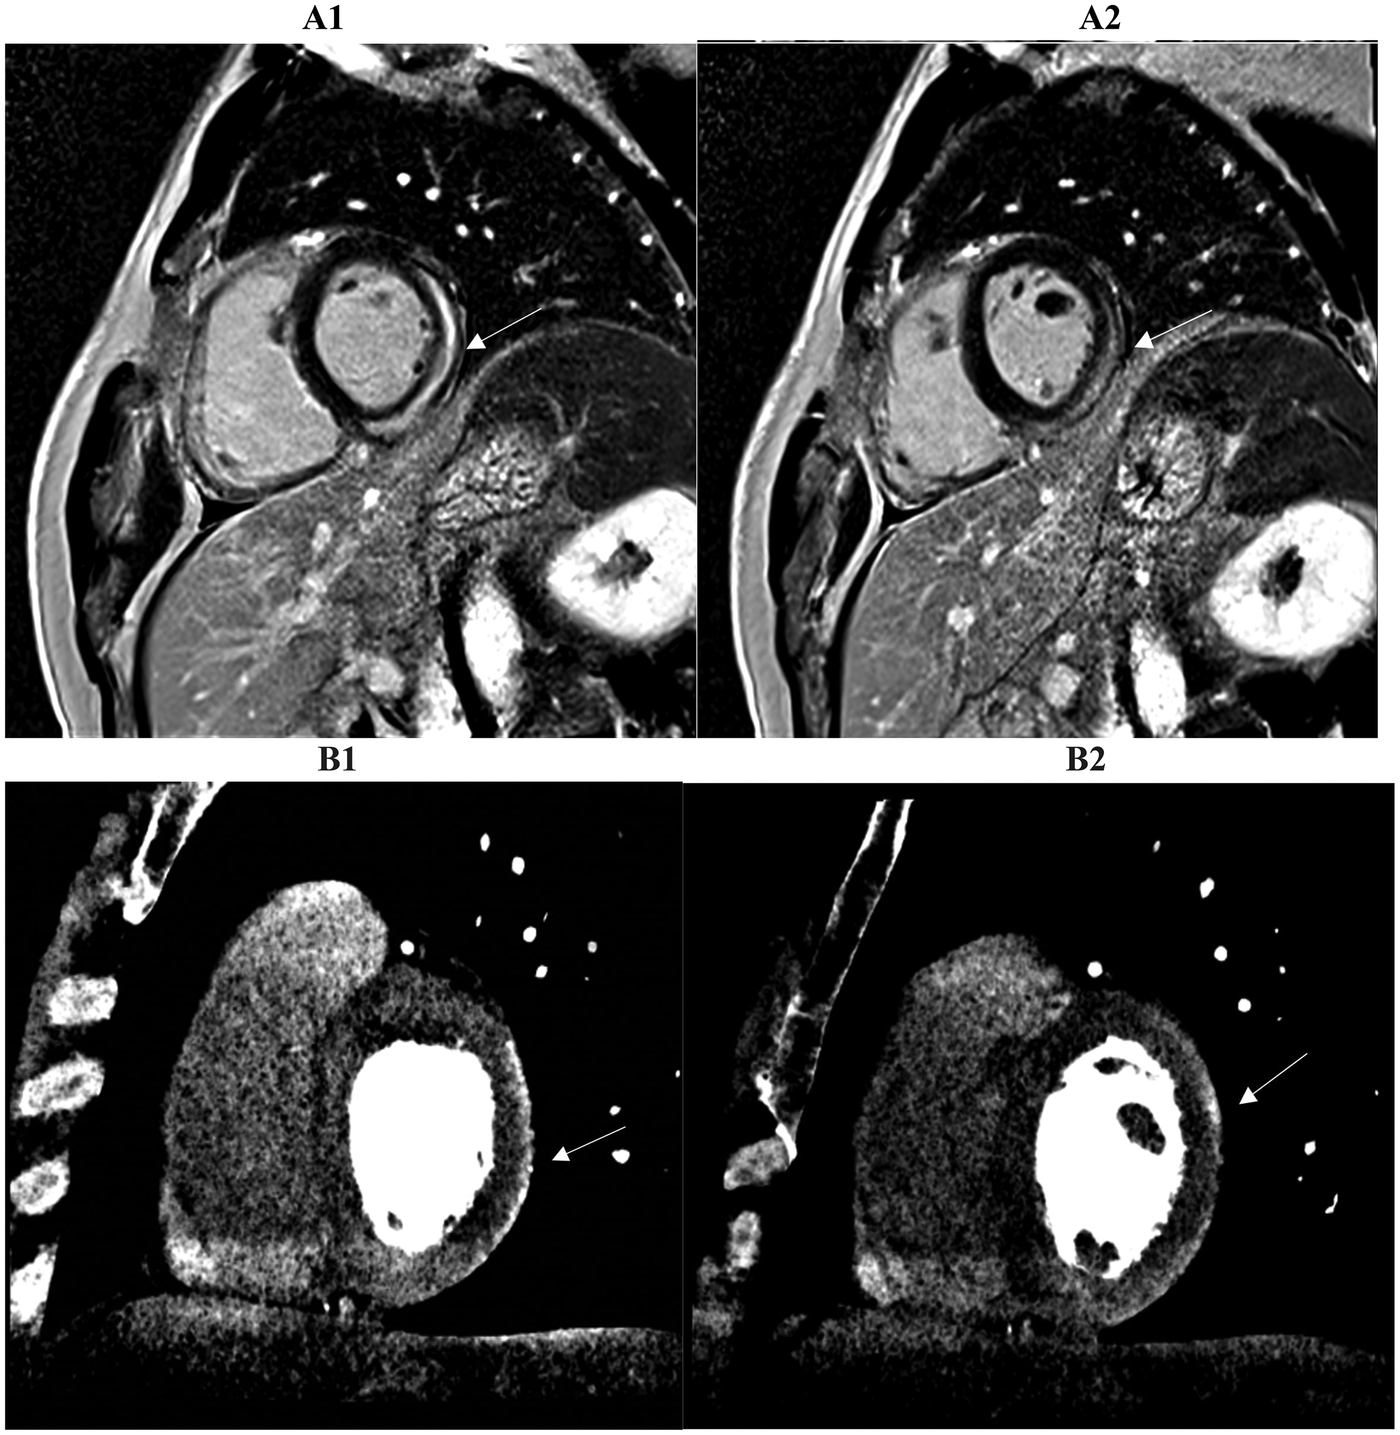

Figure 5

Two consecutive basal and mid-basal short-axis images demonstrate a typical subepicardial scar of the inferolateral wall highlighted by late iodine enhancement (LIE) (B1, B2). The CCTA findings suggested myocarditis and were confirmed by cardiac MRI performed within 14 days of the acute event. A subepicardial-intramural stria of late gadolinium enhancement (LGE) is seen on the basal and mid-basal short-axis LGE images (A1, A2), with 83% spatial agreement between the two techniques based on the matching presence or absence of myocardial enhancement in the corresponding segments (arrow).

A stronger correlation between the scar tissue burdens measured by LIE and LGE was found in our patients with ischemic cardiomyopathy with an agreement (100%) between both imaging techniques, regardless of the physician's experience level (Figure 6). This strong agreement in identifying the presence or absence of scar tissue felt to 25%–83% for non-ischemic cardiomyopathy scars, like myocarditis, in which CMR remains the gold standard for detailed tissue characterization and diagnostic certainty.

Figure 6

A strong correlation of scar tissue burden is observed between late gadolinium enhancement (LGE) (A1, A2, top row) and late iodine enhancement (LIE) (B1, B2, bottom row) in two- and three-chamber long-axis views. Both imaging methods demonstrated complete concordance (100%) in identifying myocardial segments showing enhancement, indicating full agreement in the detection of scarred tissue in a patient with suspected ischemic cardiomyopathy. Arrows mark the areas involved.